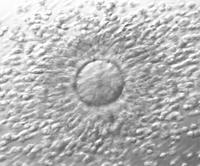

Tras la fecundación los embriones se siguen en el laboratorio. Son supervisados por los biólogos y monitorizados para asegurarse de su correcto desarrollo en las fases iniciales. Se mantienen en incubadoras, a temperatura constante, en medios de cultivo adecuados para su correcta evolución.

Entre dos y tres días más tarde se procede a su evaluación y selección para ser transferidos a la paciente y/o vitrificados. No todos se desarrollan correctamente por lo que algunos interrumpirán su desarrollo y serán descartados para la transferencia.

En algunos casos, por diferentes motivos, se considera indicado alargar el cultivo de los embriones hasta una fase más avanzada del desarrollo, denominado "Blastocisto", y se transferirá en el día 5º ó 6º de desarrollo.